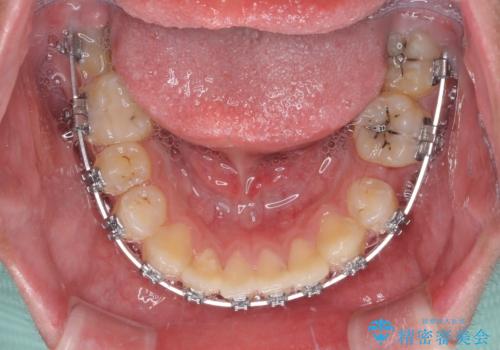

- 矯正装置

- メタルブラケット

矯正治療は、むし歯が酷く抜歯が望ましい歯を1本抜歯して、ワイヤー装置にて整えることとしました。

むし歯が多かったため、ワイヤー矯正中に処置したむし歯が悪化することが懸念されましたが、歯磨きをしっかりと行ってくれたため、とても良好な状態を維持することができました。